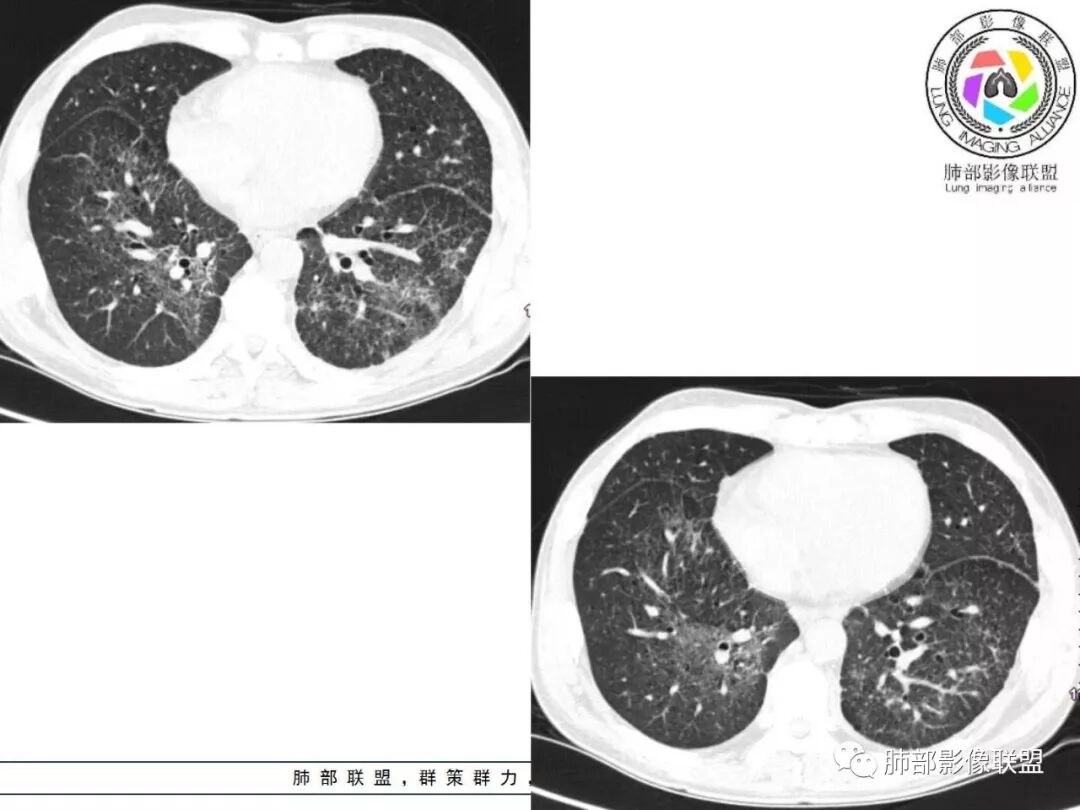

胸部CT:两肺弥漫病灶,磨玻璃影,少许实变,部分累及胸膜,磨玻璃区可见囊?少许胸腔积液,两肺可见结节,支气管血管束增粗,小叶间隔增厚,支气管走形有扭曲扩张,可见纤维化。气肿、大泡。考虑:感染性病变,PCP?查下HIV,CD4,G等。鉴别结核、结缔组织病肺浸润。

患者中年男性,发热1月,体温38℃-39℃,峰值40℃,无畏寒、寒战,伴黄痰,CRP升高明显,降钙素原稍升高,血沉、血糖正常。胸部CT:两肺弥漫病变,磨玻璃影+点片渗出,部分累及胸膜,磨玻璃区边界清楚,少许胸腔积液,两肺支气管血管束增粗,小叶间隔增厚,部分支气管走形有扭曲扩张,可见肺气肿、右肺尖肺大泡及部分纤维化改变。综合考虑:感染性病变。结核或PCP可能性大,鉴别风湿免疫、结缔组织疾病肺浸润和腺癌等恶性病变。

双肺弥漫性病变,多发磨玻璃密度及小叶间隔增厚,大部分沿支气管血管束分布,伴支气管轻度扩张,以午后及晚上发热为主,考虑感染性病变,间质性结核可能大,另双肺多发肺气囊,LIP待排

中老年男性,双肺弥漫性病变,呈网状、斑片及大片状,实变影及磨玻璃影相间,部分病灶区支气管扩张,并见多发小囊状或蜂窝状透亮影,中央间质增厚,气管前单发小淋巴结。考虑淋巴细胞增生性病变?粘膜相关性淋巴瘤(MALT)或淋巴细胞间质性肺炎(LIP)?鉴别机化性肺炎(OP)及结核(TB)。

双肺肺气肿背景,双肺弥漫分布磨玻璃及实变密度,病灶沿血管支气管束及胸膜下分布为主,部分病灶以平直收缩为主,局部支气管稍扩张,管壁增厚,小叶间隔增厚,结合临床病史,考虑炎性病灶,感染伴病灶机化?结核?NTM?

中老年男性,发热1月余,双肺弥漫性病变,多发网格、结节、斑片状实变影及磨玻璃影,胸膜下及中轴间质都受累,支气管血管束增粗、变形,支气管扩张,叶间裂及小叶间隔增厚,整体间质性改变明显,考虑结核?OP、LIP?进一步除外PCP、肿瘤、结节病等。

2. 肺气肿背景(小叶中心性肺气肿);双肺多发病灶整体沿血管支气管束及胸膜下分布,以上叶及下叶背段分布为主,有实变及GGO,边界清楚,有树芽,小叶间隔及中央间质增厚,叶间裂见到多发结节,部分支气管不规则牵拉扩张,提示病灶纤维化明显,结合临床病史,考虑病灶为间质性感染,肺门及纵隔内有钙化淋巴结,小叶间隔结节,考虑淋巴道增值性疾病可能,综合常规要怀疑间质性肺结核。